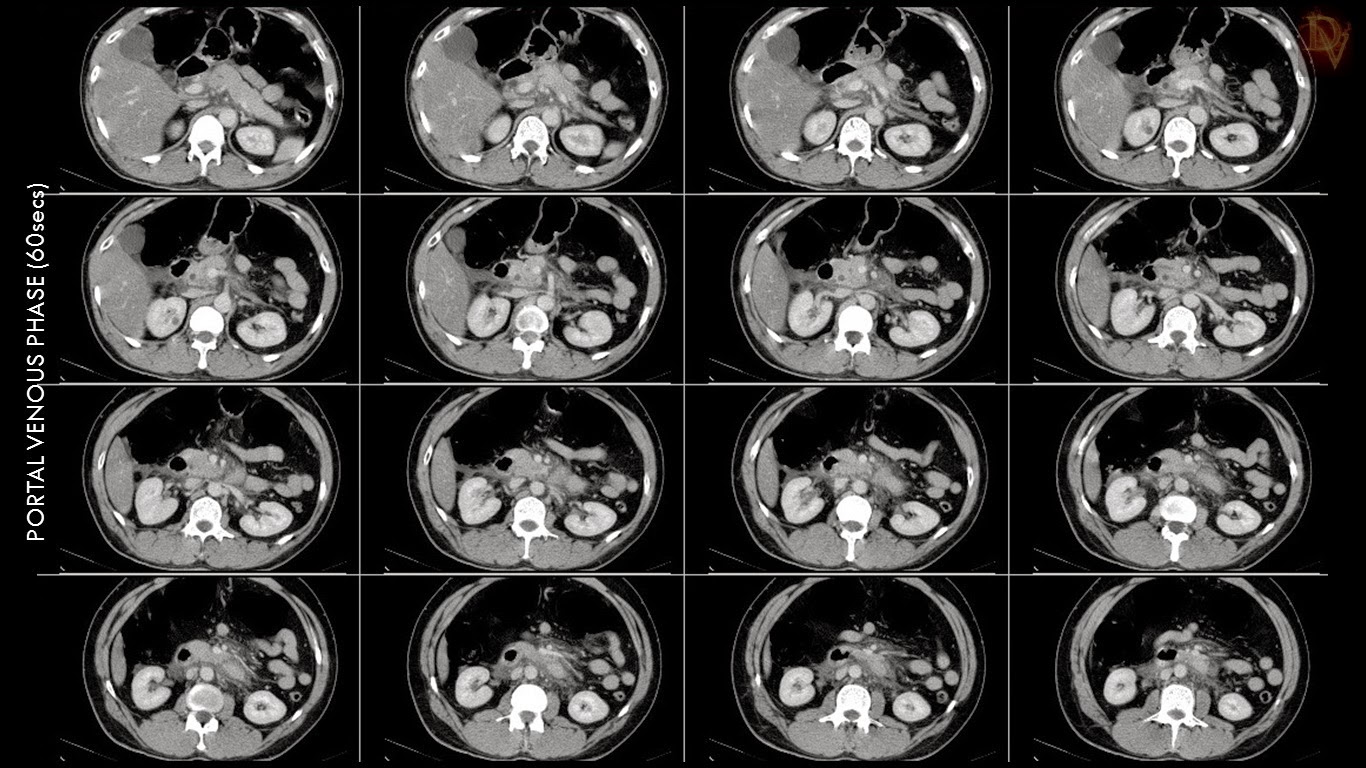

pancreas eurorad divisum pancreatitis acute axial diffuse peripancreatic arrows.

divisum pancreas pancreatitis acute hemorrhage radiology enhancement duct.

pancreas divisum pancreatitis acute hemorrhage hyperdense contrast showed enhancement area.

pancreatitis acute pancreas divisum hemorrhage radiology ultimate march.